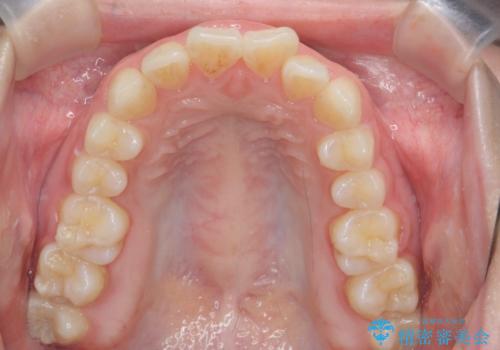

- ねじれの目立つ前歯の見た目を改善したいと矯正治療を希望され来院されました。

がたつきの改善をマウスピース矯正インビザラインで行っていきます。

ガタつきの改善はもちろん、歯列全体のアーチも放物線状にきれいに排列し審美性を向上させることができました。